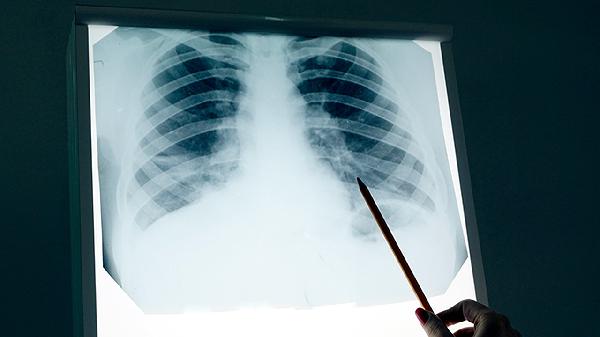

早期肺癌增强CT的八种表现有哪些

早期肺癌在增强CT中主要表现为磨玻璃结节、实性结节、混合磨玻璃结节、空泡征、支气管充气征、胸膜凹陷征、血管集束征和分叶征八种特征性影像学改变。